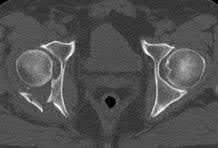

Figures A-C: The initial radiographs reveal the posterior subluxation of the talus with associated posterior subluxation of the fibula without significant coronal plane deformity. This deformity should raise the suspicion of a Bosworth fracture-dislocation, especially if closed reduction is not successful. Figures D and E: Axial CT images demonstrating Bosworth fracture-dislocation of the fibula entrapped behind the tibia. Also, note the fracture extension to the posteromedial rim in this posterior pilon variant.

The rare Bosworth fracture-dislocation is a posterior dislocation of the fibula which becomes entrapped behind the tibia. As demonstrated in this vignette, these injuries are extremely difficult to close reduce secondary to the ridge of the posterolateral distal tibia. The irreducible nature of this injury is a known risk factor for the development of compartment syndrome. The CT images further demonstrate fracture extension to the posteromedial rim (“posterior pilon variant”). In this situation, the only effective method to reduce the fracture is through an open posterolateral approach with the interval between the flexor hallucis longus and the peroneal tendons. This is the same approach that is utilized for fixation of the posterolateral fragment and fibula. Loss of dorsiflexion has been demonstrated following this fracture pattern with posterior fixation. The positioning of the plates in Figure F suggests the

utilization of a posterolateral approach.